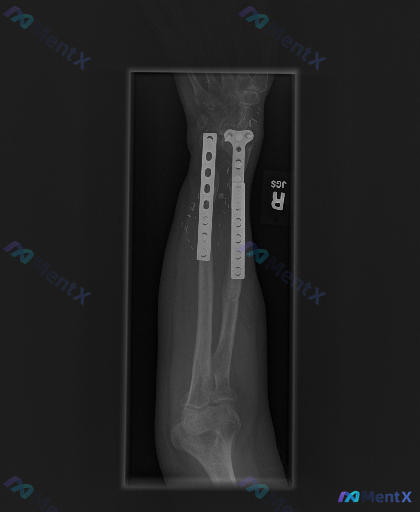

各位骨科同道,今天分享一个右前臂远端双骨折内固定术后的复查病例,一起探讨影像表现的临床意义。 病例资料 患者为右前臂远端桡骨、尺骨双骨折切开复位内固定术后,目前为术后复查阶段。 影像表现摘要 1. 内固定情况:桡骨远端见解剖锁定钢板,尺骨远端见直型接骨板,多枚螺钉固定,内固定物位置稳固,未见明显断钉...

整理到一个右前臂尺桡骨骨折术后的影像学病例,资料如下: 基本背景 右侧前臂(桡骨与尺骨)双骨折术后内固定状态。 影像学表现 1. 内固定:桡骨、尺骨干均可见钢板+螺钉固定,钢板跨越骨干中段,目前钢板螺钉位置固定,未见明显移位、松动或断裂征象。 2. 骨折愈合:骨折断端处骨痂形成尚不明显(骨痂影较淡)...